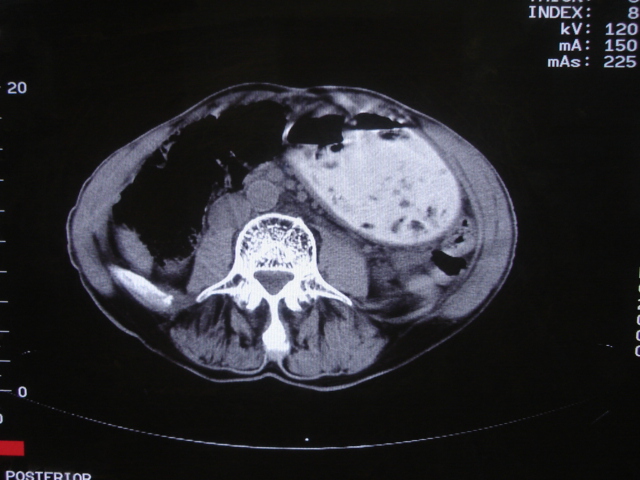

以下是引用深泽交通医院在2008-7-17 12:39:00的发言:[br]胃下垂;胃窦占位

以下是引用杀毒软件在2008-7-17 16:45:00的发言:[br][br] 建议胃镱检查!考虑胃窦部占位